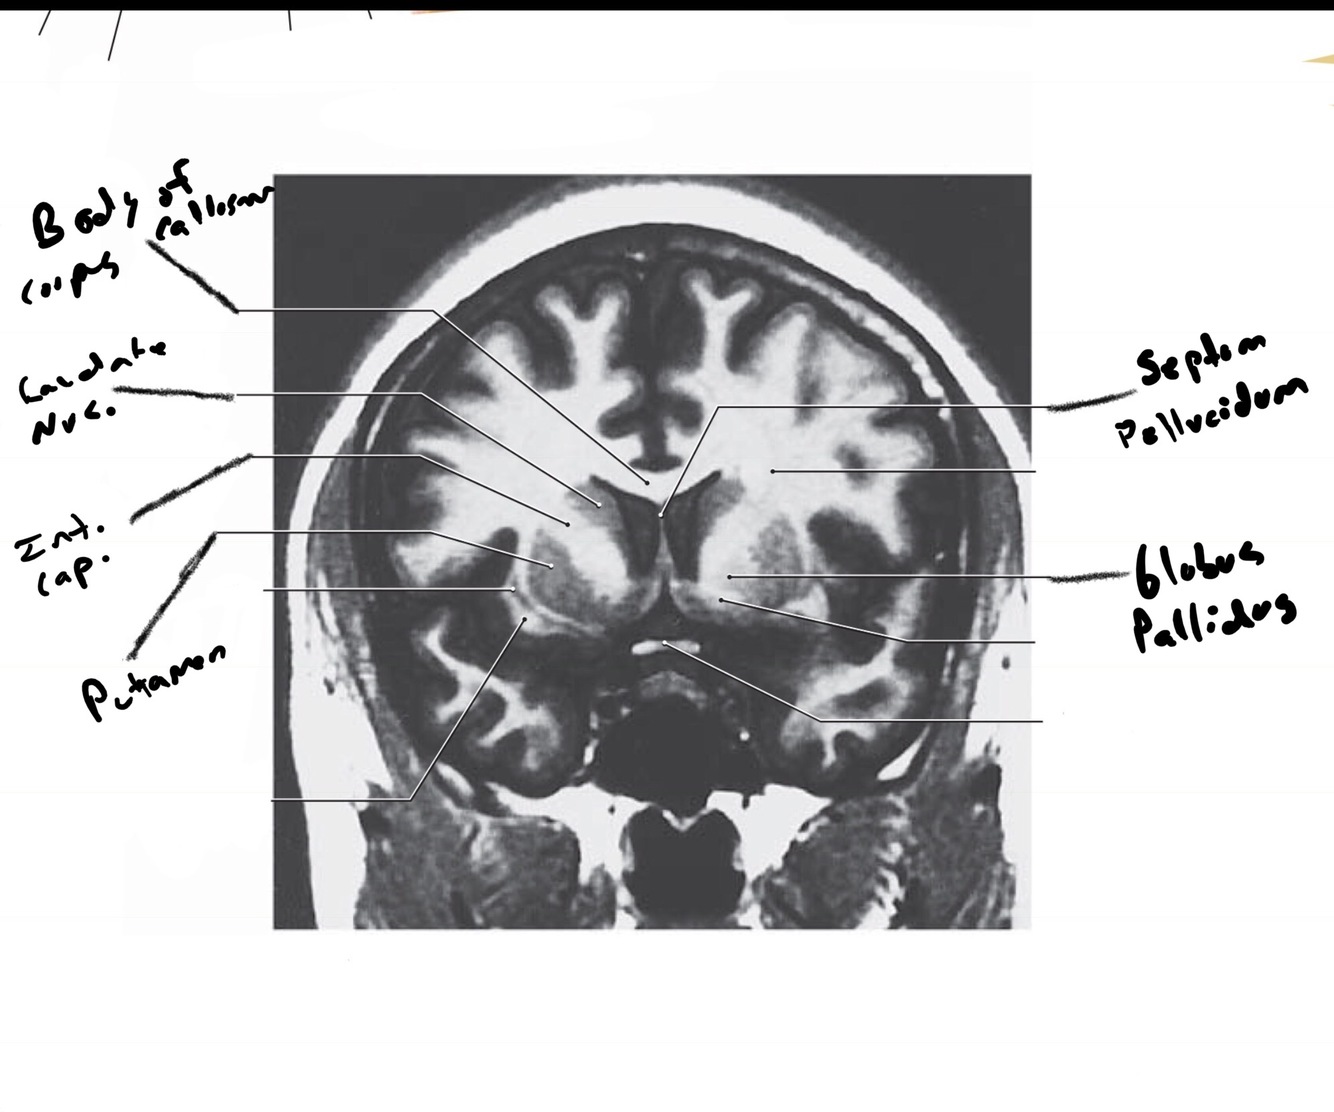

The structure indicated by the red line is?

The structure indicated by the red line is? BONUS: SYMPTOMS IF THERE IS A LESION

motor problems